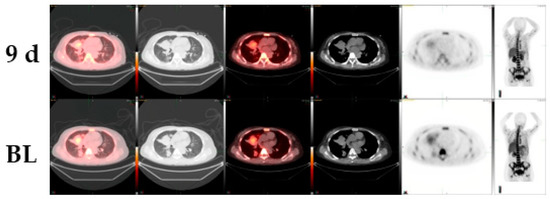

Patient 3: The third case study is a 59-year-old female with a diagnosis of EGFR-negative lung adenocarcinoma. The patient received cisplatin, vinorelbine, pemetrexed, and cetuximab as part of standard therapy and was eventually enrolled on an MDM2 inhibitor. Herein, a nine-day pre- and post-targeted therapy image of the right middle lobe mass comparison was done using CT and 18F-FLT PET/CT. While CT demonstrated a change of 6% tumor size from 5.1 cm × 4.4 cm to 4.8 cm × 4.6 cm, 18F-FLT PET/CT showed a reduction of 31% from 3.6 to 2.5 SUVmax (Figure 3).

Figure 3. 18F-FLT PET/CT scans shows early response to MDM2-inhibitor targeted therapy whereas the conventional CT scan images do not show any responses in a patient with EGFR-negative lung adenocarcinoma (BL, baseline; 9d, at 9 days post therapy).